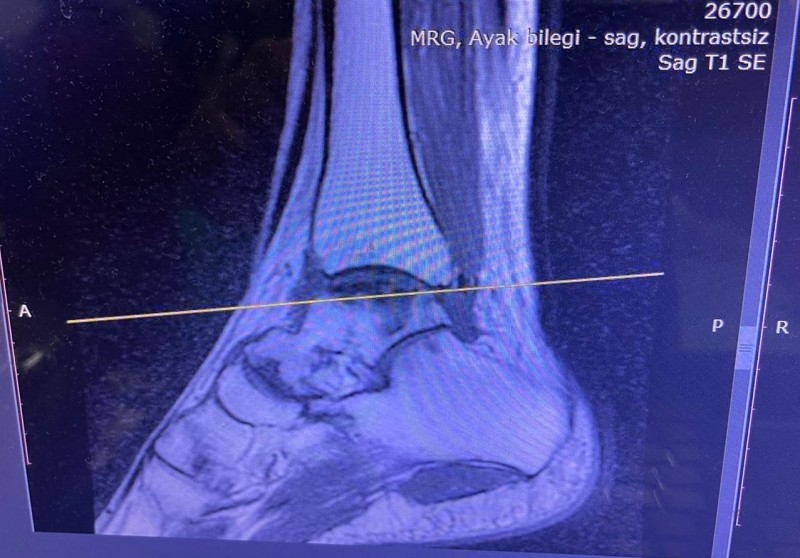

Hastanede yapılan, “Balıkesir’de ilk” nitelikli işlemlerin bir yenisi de Ortopedi ve Travmatoloji Anabilim Dalı Öğretim Üyesi Doç. Dr. Aziz Atik tarafından gerçekleştirildi. Gerçekleştirilen ameliyatla ilgili bilgiler veren Ortopedi ve Travmatoloji Anabilim Dalı Öğretim Üyesi Doç. Dr. Aziz Atik; “Lenf kanseri olan 21 yaşındaki hastamız lenf kanseri tedavisi görerek sağlığına kavuşmuş ancak ilerleyen zamanlarda aldığı tedavilerin yan etkisi olarak ayak bileği kemiğinde çürüme meydana gelmiş. Bize başvuran hastamızın eklem yüzeyi bozulmuş ve hastamız yürümekte zorlanıyor, topallıyordu. Büyük bir lezyonu olan hastamıza büyük lezyonlarda uygulanan en iyi tedavi yöntemi olan ve nadir olarak yapılan bir ameliyatla kadavra donörden kemik ve kıkırdak doku nakli gerçekleştirdik.” ifadelini kullandı. Ülkemizde kemik ve kıkırdak bankası olmadığının altını çizen Doç. Dr. Aziz Atik, yurt dışından bir donör bulmak için çalışmalar yaptıklarını ve yurtdışından kemik bulunduğunda ivedi bir şekilde ameliyatı gerçekleştirdiklerini söyledi. Ameliyatın son derece başarılı geçtiğini belirten Doç. Dr. Aziz Atik, güzel bir eklem düzeyi elde ettiklerini ve ameliyatla genç bir insanın topallamadan, ağrısız yürümesini hedeflendiklerini dile getirdi.